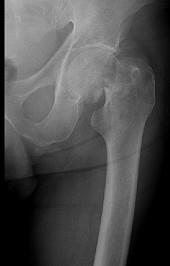

问题 图示股骨颈骨折为Garden第几型 ( )

选项 A、Ⅳ型 B、以上都不是 C、Ⅱ型 D、Ⅲ型 E、Ⅰ型

答案 A